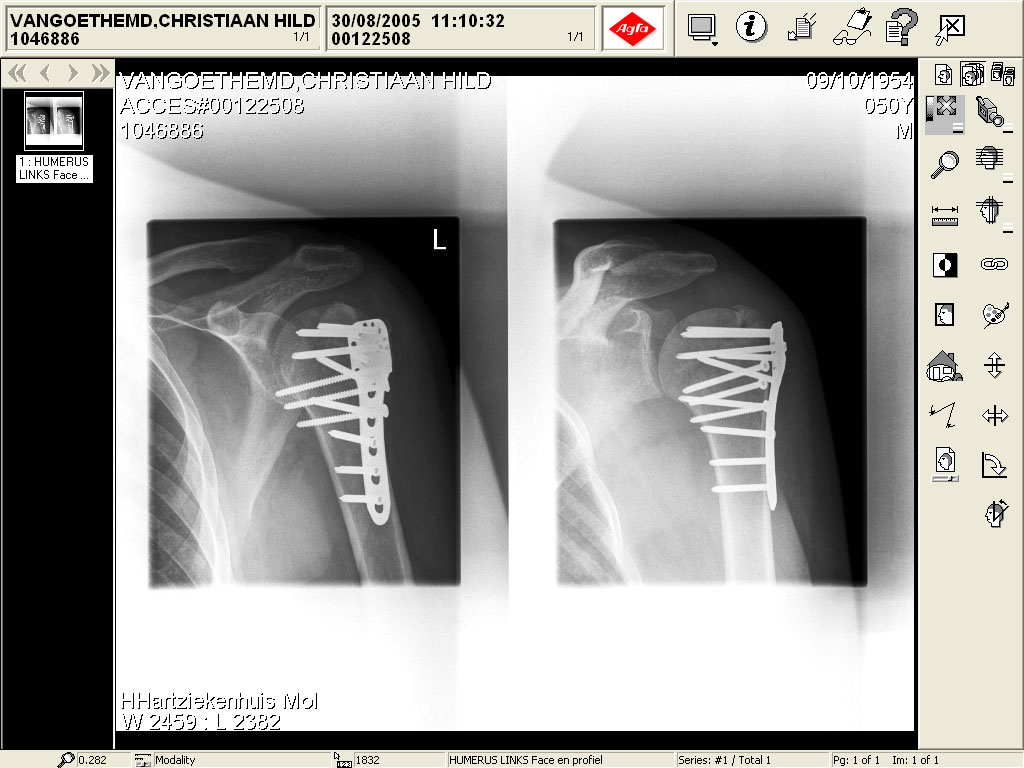

banana's armafter crash last year with my s4r